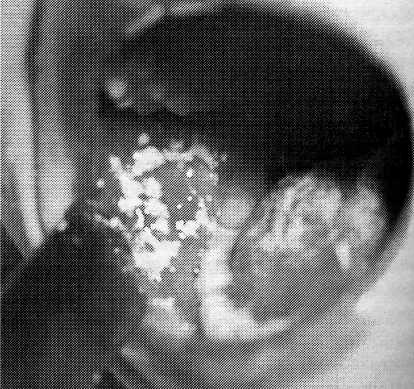

I. Рис. 144. Кандпдозная инфекция. Наложение на слизистой оболочке щеки и языке — «молочница».

или инфекционных заболеваний. Начинается стоматит с сухости и гиперемии слизистых оболочек, потери аппетита, небольшого ухудшения общего состояния. При первичном стоматите осмотр полости рта выявляет творожистые белые или кремовые наложения, располагающиеся на слизистой оболочке щек (рис. 144), десен, твердого и мягкого неба (рис. 145), внутренней поверхности губ. При вторичном стоматите поражения более глубокие и наложения на слизистой оболочке полости рта более толстые и плотные, чем при первичном процессе; отмечаются эрозии и изъязвления слизистой оболочки. В части случаев стоматит проявляется только гиперемией слизистой оболочки полости рта без инфильтративной реакции. У некоторых больных стоматиты приобретают форму язвенного процесса с поражением твердого неба и становятся причиной генерализованного кавдидоза.